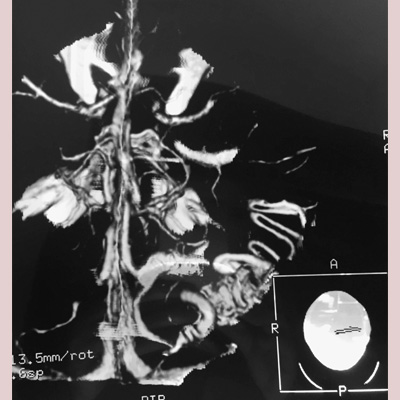

Brain Arteriovenous Malformations (AVM), as well as other Vascular Malformations are resected with sophisticated Microsurgical techniques in appropriately selected cases, or referred for Endovascular Embolization, Stereotactic Radiosurgery (SRS), or a combination of these treatment modalities with high success rates and safety and efficacy.